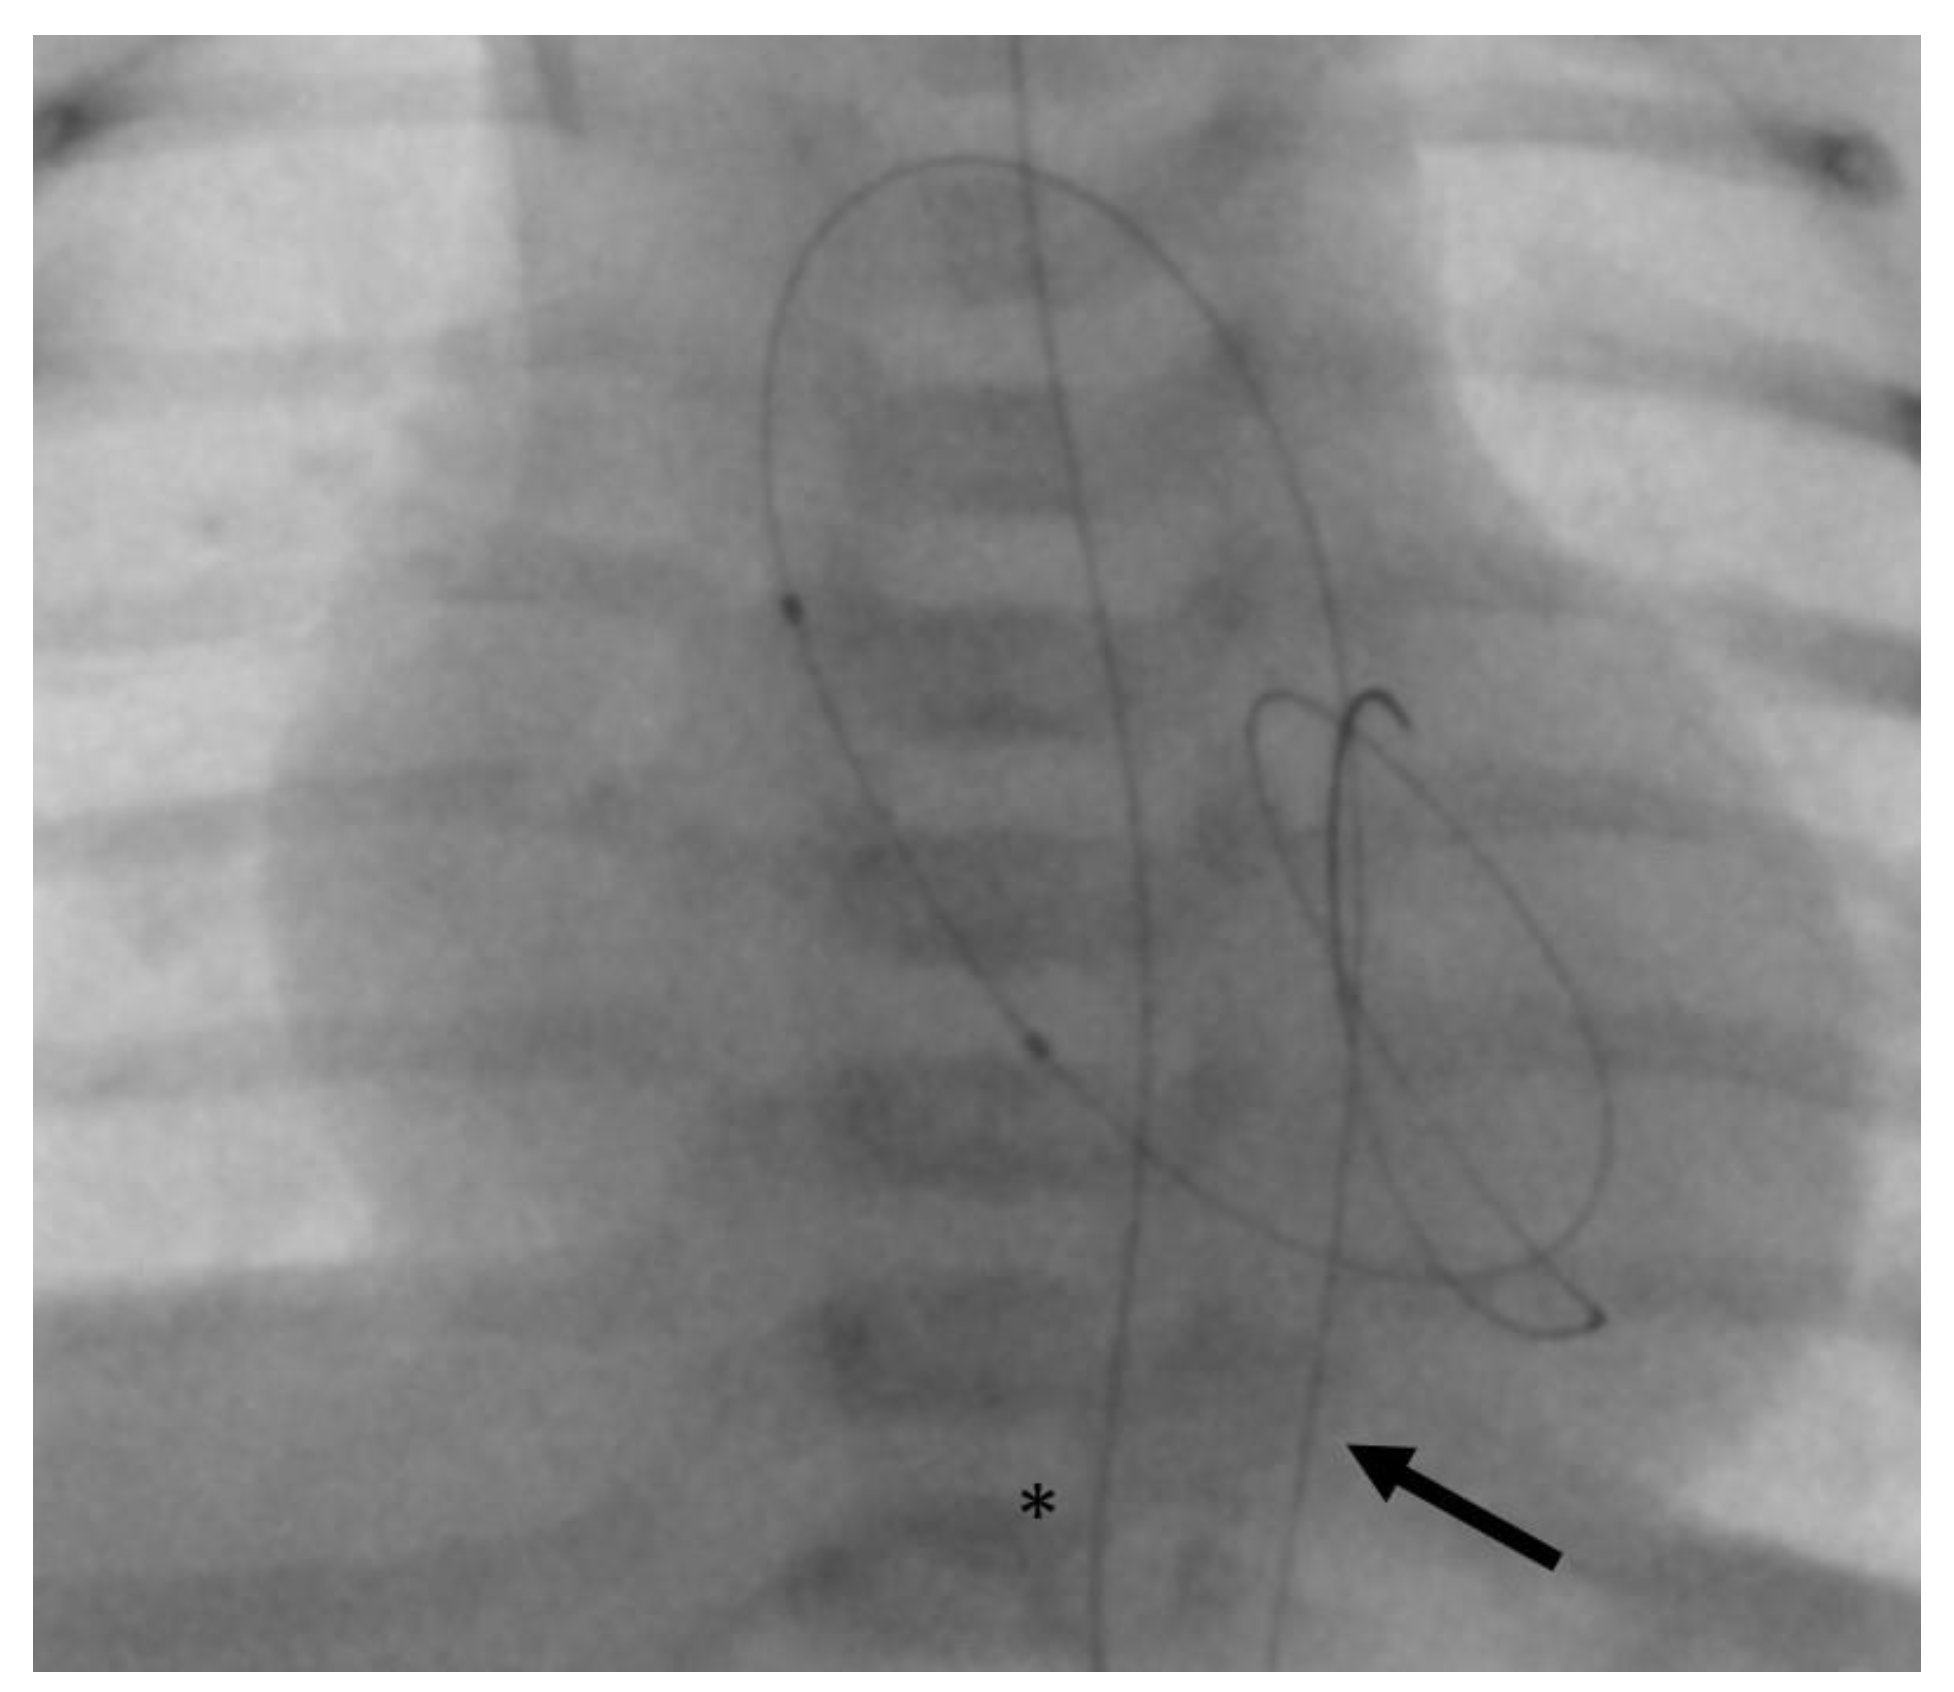

- In case 2, there was an air embolism in the left ventricle during the patient’s first catheterization. Due to depressed LV function with low contractility, the air bubble remained ventrally in the LV (Figure 8), where we managed to extract it with the catheter.